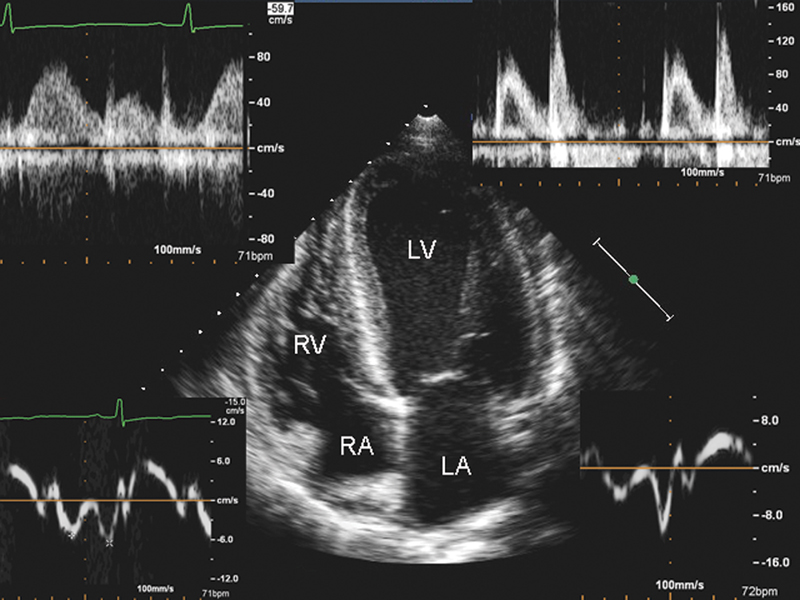

فحوصات تشخيصية لبعض امراض القلب والشرايين التاجية